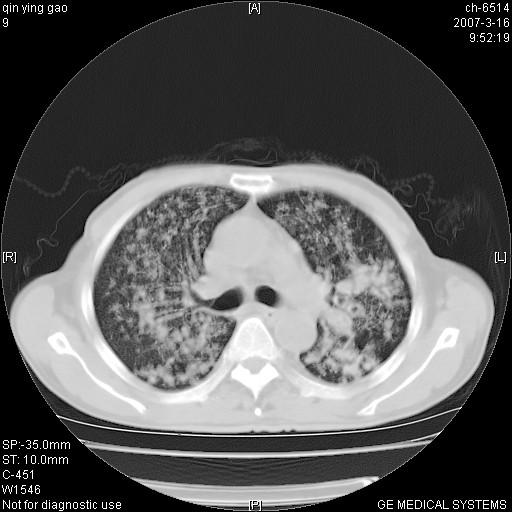

标题: CT7174:两肺弥漫性病变,请讨论

男,64岁.乏力2个月,畏寒、发热1月余。体重下降。血沉加快,白细胞不高。

两中上肺见有广泛新老不一的结节灶,并伴有纤维索条影,血沉加快,白细胞不高,首先考虑结核。

双肺可见大小不等结节状密度增高影,密度不均,分布不均(双肺上叶为著),亚急性血行播散性肺结核.

(本例特征:以大小不等结节为主,主要分布在双上肺,并部分病灶融合成较大结节,期间搀杂诸多细小结节。从病灶特点与分布形式分析,更趋向于感染。)

男,64岁.乏力2个月,畏寒、发热1月余。体重下降。血沉加快,白细胞不高。 双肺可见大小不等结节状密度增高影,密度不均,分布不均(双肺上叶为著),亚急性血行播散性肺结核.

以双肺上叶为主的弥漫型斑片状密度增高影,边界欠清晰,其中伴有钙化灶,病人有发热史,首先考虑感染性病变:1特殊类型感染,2结核。建议治疗后随诊复查,除外肺泡癌

两中上肺见有广泛分布大小不一的结节灶及斑片状影,部分融合,双下肺未见异常密度影,纵隔无明显肿大淋巴结,血沉加快,白细胞不高,首先考虑结核。 建议结合ppd检查或痰培养排除其他非特异性炎症。

中上肺野密布棉团状影,以胸膜下区为界,边缘模糊,可能是小叶或腺泡渗出及实变。全肺野弥漫分布网线样影及细小粟粒样影,可能是细支气管炎及间质内炎症。综合分析应首先考虑气道播散性感染,而肺内多处斑点性钙化,强烈提示陈旧结核复发并支气管播散。建议详细讯问病史